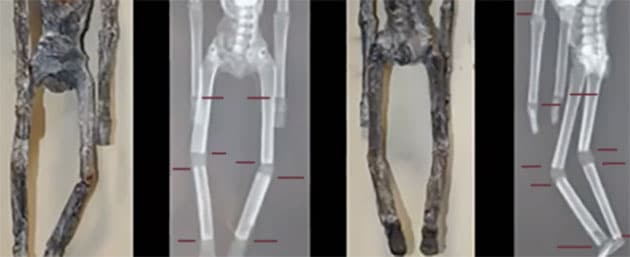

Zu „Material und Methoden“ erläutert Estrada Moreno, dass hierzu Röntgenaufnahmen der besagten Mumien, ebenso wie Aspekte der vergleichenden Anatomie und Analysen mit Infrarot-Spektroskopie zum Einsatz kamen, mit der die Zusammensetzung von Material und Stoffen zerstörungsfrei und von außen durchgeführt werden kann.

Zwar zeigen die Röntgenaufnahmen (Abb. 02 u. 03), dass dieser Körper auf Knochen basiert, doch sind viele dieser Knochen, gerade jene der Gliedmaße, teilweise einfach nur abgeschnitten und stumpf zusammengesetzt wurden. Es fehlen funktionale Gelenke. „Das einzige, was an diesem Körper stimmt, ist die vollständige Wirbelsäule.“

Anhand der Röntgenaufnahme (Abb. 36) ist zu erkennen, dass dieses Wesen überhaupt keine Halswirbel oder sonstige Halsknochen besitzt. Zugleich gibt es aber auch keine Anzeichen für eine diesen Hals und damit den Kopf stützende Muskulatur. Eine weitere anatomische Katastrophe ist der Einbau der Oberschenkel, die wie Arme platziert wurden. Zudem verfügt das Wesen über keine wirklichen Gelenke. Mit Ausnahme des Schädels stammen auch hier alle Knochen von Menschen – in diesem Fall von noch nicht ausgewachsenen Menschen, da sich an den Knochen Wachstumslinien erkennen lassen. Anhand dieser Merkmale schließen die Wissenschaftler, dass der Mensch, dessen Knochen hier verwendet/missbraucht wurden, Ernährungsprobleme hatte.

Aus den Röntgenaufnahmen geht ebenso hervor, dass auch diese Mumie keine wirklich funktionalen Gelenke besitzt. Mit dieser Anatomie hätte sich ein solches Wesen kaum bewegen können, da Knochen teilweise direkt aufeinanderstoßen, abgeschnitten und aufeinander gekantet wurden. Zudem ist ein Bein wesentlich länger als das andere.